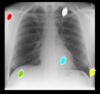

- e.g. below: increased left lung whiteness due to rotation